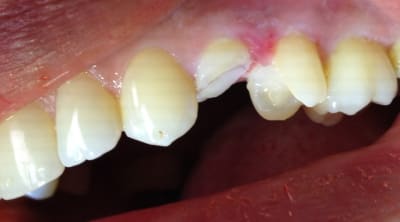

Alors comment traiteriez vous cette 24 asymptotique, qui présente un enorme délabrement sous gingival , notez que l'émail n'est plus soutenu par la dentine à aucun endroit ?

1ère séance remontées de la marche distale au compo flow + compo de restauration / réalisation d'un IDS , le tout sous digue bien sur (voir radio jointe , désolé à l'envers))

Voici les photos toutes fraiches de ce matin.

Vos critiques sont bien sur les bienvenues je dois encore beaucoup m'améliorer sur les prises de teintes, et je m'y attelle en ce moment,, par contre en ce qui concerne la pérennité de la restauration…..ma patiente a sa dent bien vivante, aucun joint sous gingival , possibilité de réaliser une endo dans le futur sans détruire la restauration existante si besoin, possibilité re refaire un onlay dans quelques années si ça casse, toujours sur dent vivante…. bref la liste des avantages est très longue par rapport au classique endo-IC-CCM.